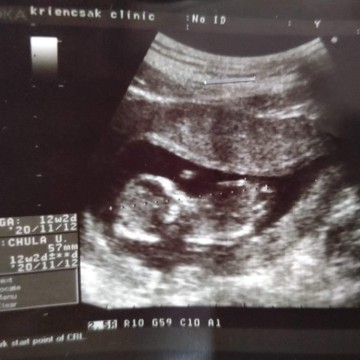

12w